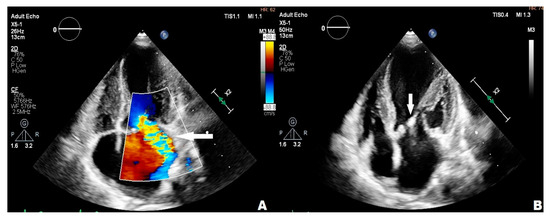

3.2. Case 2